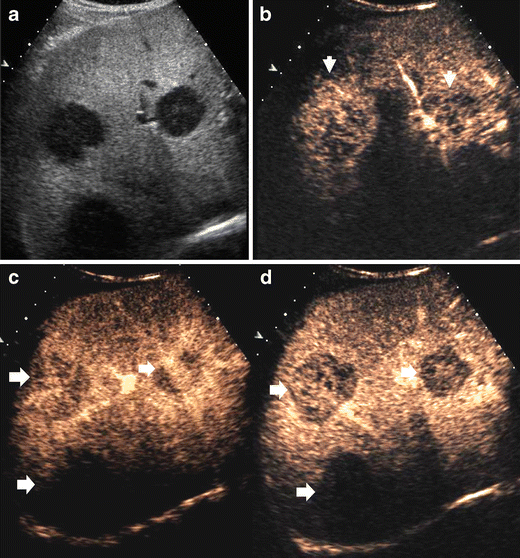

CEUS provides a benign or malignant diagnosis based on focal liver lesion enhancement patter at arterial phase and lesion vascularity at portal—late phase in comparison to the adjacent liver parenchyma (Figs. 1 and 2). Malignancies typically show a low echo-signal intensity at late phase [4, 5, 8], regardless of whether they are hyper- or hypovascular in terms of their arterial supply (Fig. 1). The late phase, with or without hepato-specificity, was showed to be the most important for focal liver lesions characterization since benign lesions present prevalently a sustained enhancement with hyper or isovascular appearance to the adjacent liver while malignant lesions present prevalently microbubble washout with hypovascular appearance [115] (Fig. 2).

a-d Liver metastases in a 65-year-old man with rectal carcinoma. a Unenhanced grey-scale US. Metastases appear hypoechoic. b-d CEUS. Contrast specific mode: Cadence Contrast Pulse Sequencing after sulphur hexafluoride-filled microbubble injection with low transmit power insonation. Diffuse contrast enhancement (arrows) is visualized during arterial phase b with lesion hypovascularity during portal c and late phase d. A deeply-located metastatic lesions is also identificed during the portal and late phase c, d